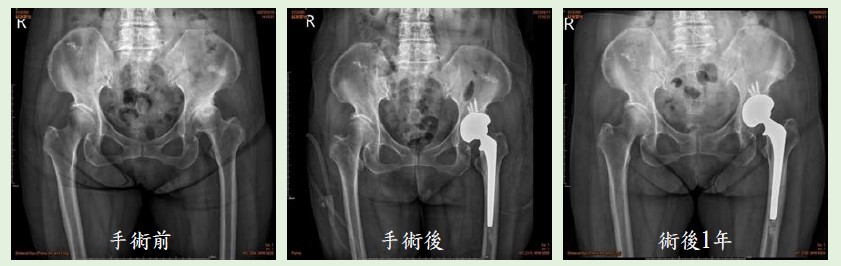

▎案例分享

75歲女性,因左側大腿行走疼痛,在外院就醫以為是腰椎退化,直到2023年3月到門診就醫。經檢查發現,左側髖關節有退化性髖關節炎,當時先採保守治療,以藥物控制配合熱敷、適當的運動,持續門診追蹤治療。 隨著病情惡化,患者左側髖部疼痛加劇,止痛藥藥效一過,即疼痛到難以忍受,且行走困難。回門診追蹤髖部X光顯示關節炎惡化,髖關節縫隙嚴重摩損。經過詳細解說病情及充分討論,於2023年4月進行人工髖關節置換手術,使用雙動式超耐磨人工髖關節系統,去除病人疼痛並恢復其日常活動的能力。目前患者復原情形良好,2024年4月回診時,行走良好無礙,重拾活力與生活品質。